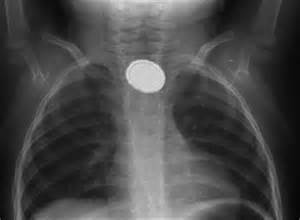

Диагностические процедуры

Первостепенное значение имеет осмотр больного и сбор анамнеза. Врач тщательно осматривает глотку, гортань и шейную область пациента, затем назначает рентгенограмму пищевода (подробнее о ней) и эзофагоскопию.

Благодаря этим методам диагностики, можно детально исследовать целостность эзофагеальной стенки и слизистой оболочки пищеводного канала, а также глубину поражения и степень осложнения патологического процесса.

На основании этих данных врач определяет необходимость хирургического вмешательства.